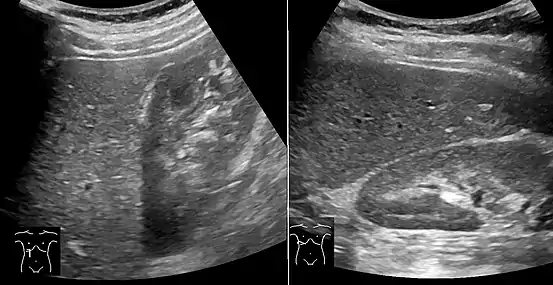

Microvesicular steatosis

Histopathology of microvesicular steatosis, with foamy hepatocytes (two annotated by arrows), as opposed to macrovesicular steatosis (insert).

Microvesicular steatosis is characterized by small intracytoplasmic fat vacuoles (liposomes) which accumulate within hepatocytes.[9] It is associated with a wide variety of conditions, including alcoholism, drug toxicity of several medications, delta hepatitis (in South America and Central Africa), sudden childhood death, congenital defects of fatty acid beta oxidation, cholesterol ester storage disease, Wolman disease and Alpers syndrome.[10]